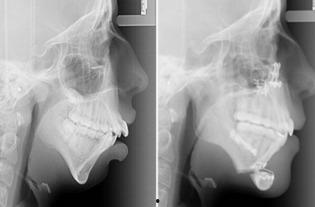

二、身体变化:直观展示病情

手术前照片最直观的作用就是展示患者的身体变化。通过这些照片,医生可以更准确地判断病情,制定手术方案。比如,一位患有甲状腺肿瘤的患者,手术前的照片清晰地显示了肿瘤的大小和位置,为医生提供了重要的参考依据。